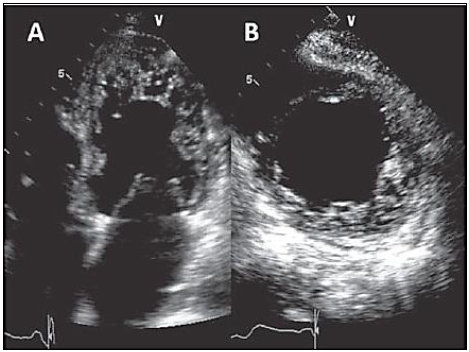

Paciente, 22 anos, com episódio prévio de Acidente Vascular Encefálico (AVE), realizou ecocardiograma transtorácico para investigação etiológica e encontrou o seguinte achado:

São critérios ecocardiográficos que fazem parte do diagnóstico, EXCETO: